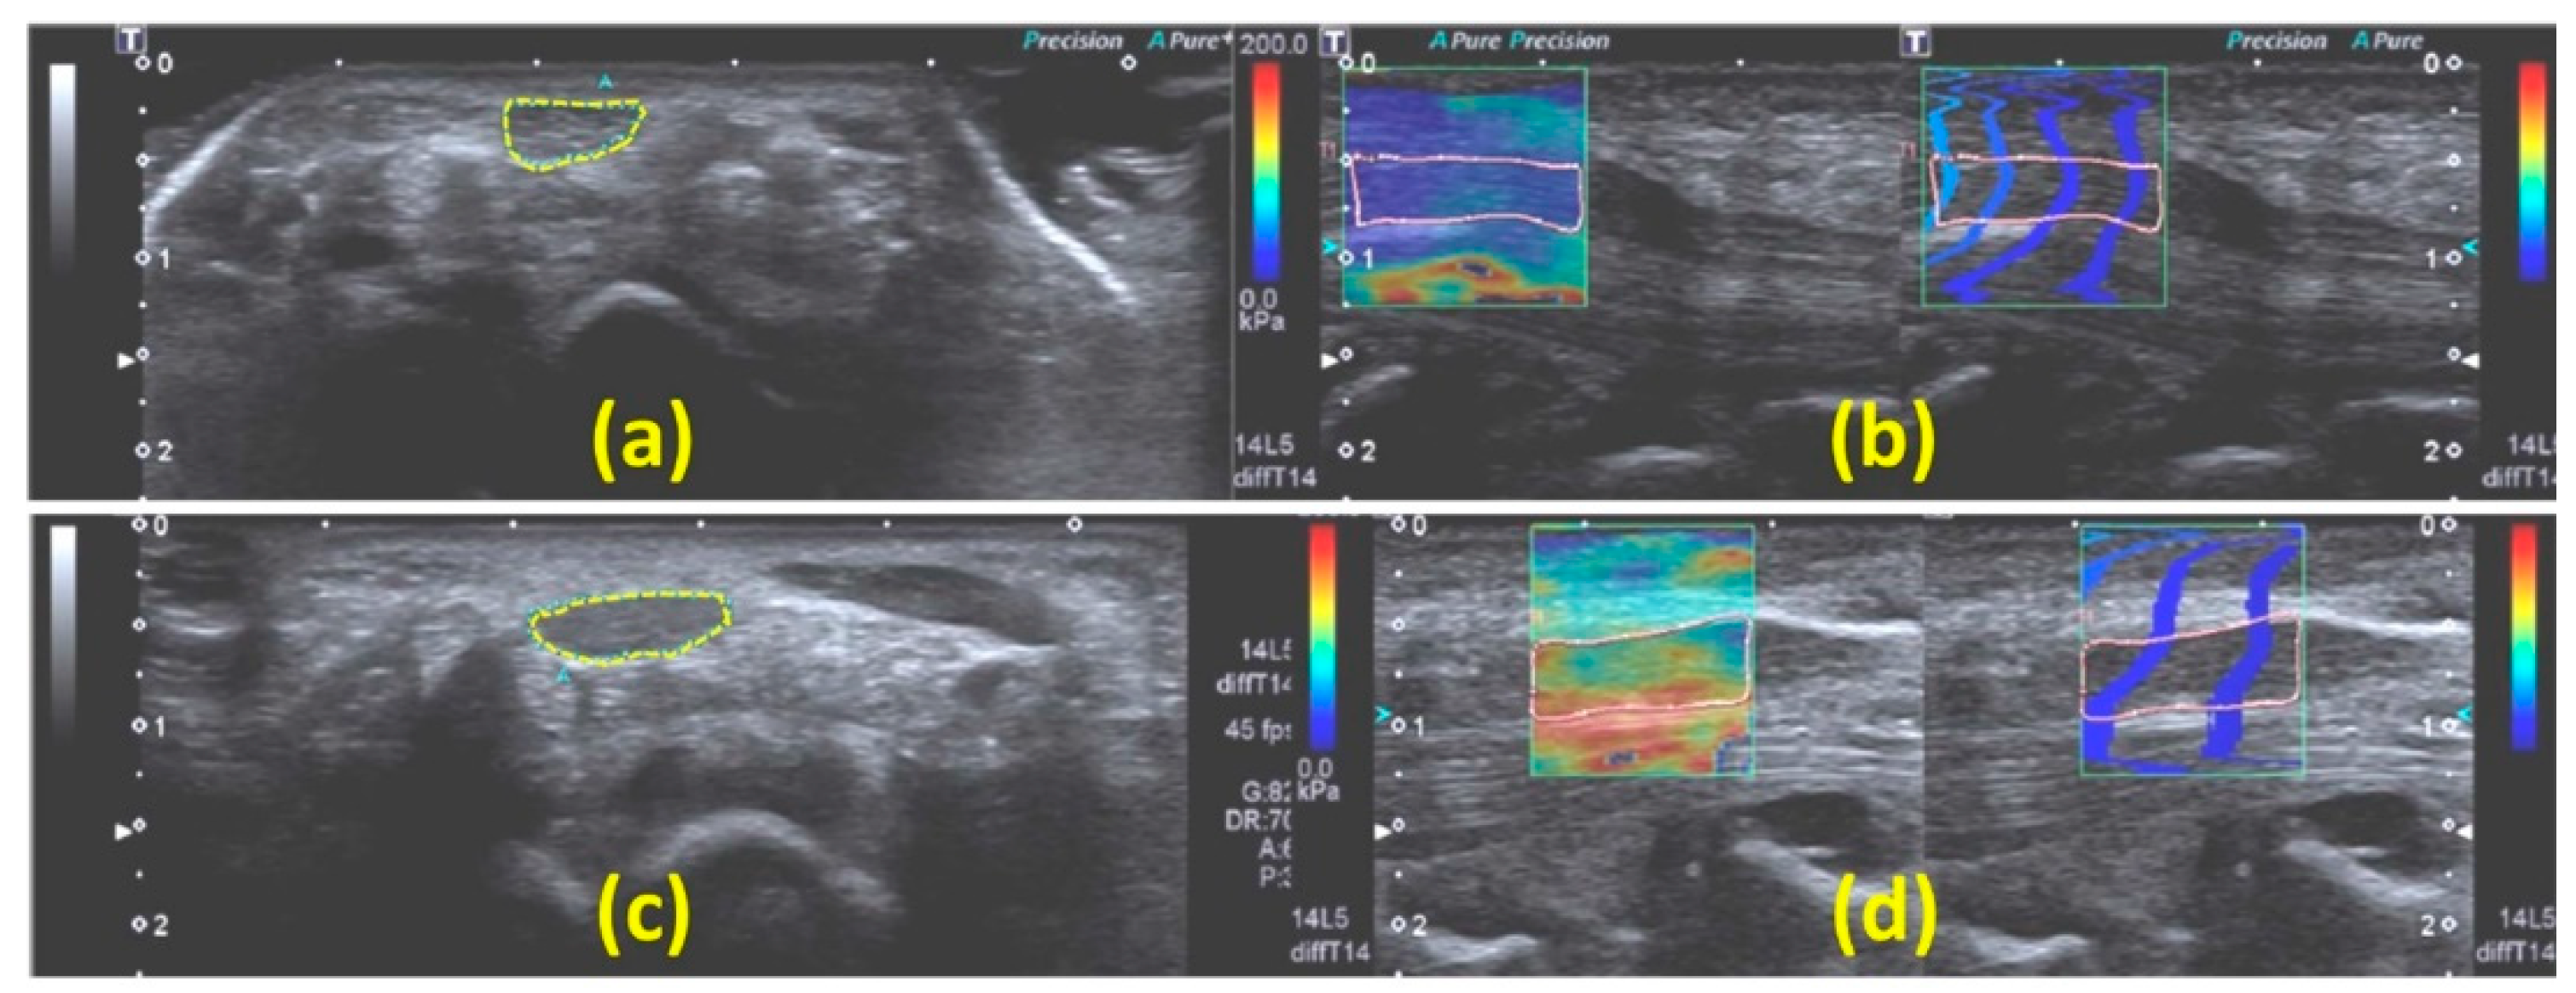

| Orman et al., 2013 [33] | To investigate the potential of strain US (pure strain) free-hand compression in detecting CTS. |

| Aplio XG, SSA 790A, Toshiba(Nasushiobara, Japan) |

|

| |

| Miyamoto et al., 2014 [34] | To investigate the capability of free-hand compression strain US technique (strain ratio (SR) with respect to acoustic coupler rubber, ACR) in detecting CTS. |

| HI VISION Preirus Hitachi-Aloka Medical (Tokyo, Japan) |